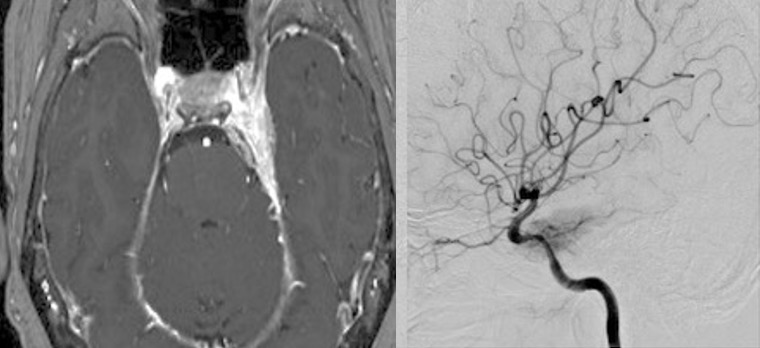

2604月、59歳女性の左海綿静脈洞内髄膜腫(複視)に対して左内頸動脈のための左STA-MCAバイパスを行いました。